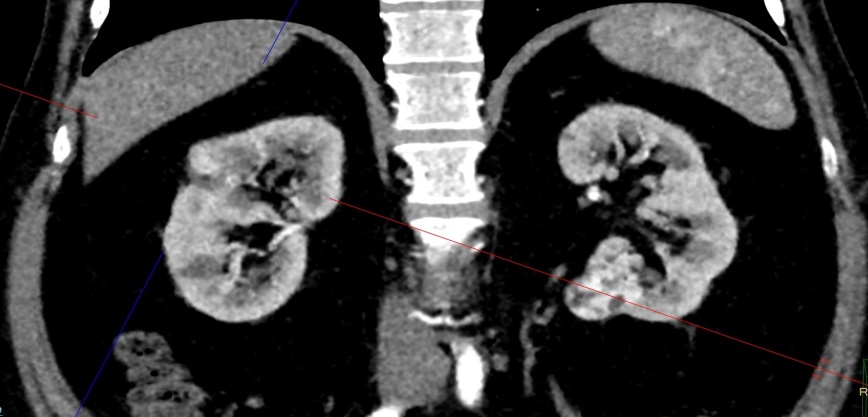

Проведен ретроспективный анализ эффективности криоаблации с 2015 по 2025 гг. у 630 пациентов больных с ПКР находящихся на лечении в ГБУ РО КДЦ «Здоровье». Возраст больных варьировал от 41 до 82 лет (средний возраст 61,5 лет). Из них 346 женщин, 284 мужчин. Критериями выбора методики криоаблации являлись наличие коморбидного статуса, конституциональные особенности и сопутствующая соматическая патология, которые ограничивали возможность выполнения органосохраняющей резекции или радикальной нефрэктомии. При этом все пациенты, независимо от возраста и пола, имели стадию T1aN0M0, а их функциональный статус по шкале ECOG составлял 0–1. Диагноз был установлен на основании клинико-рентгенологических данных (КТ почек с контрастным усилением) в соответствии с рентгенологическими критериями диагностики ПКР. Гистологическое подтверждение диагноза получали у 587 (93%) больных, остальные случаи признавались ложноотрицательным результатом. Единственная почка была у 5 больных, у 3 больных был билатеральный ПКР, в последующем такие больные получали комбинированное хирургическое лечение (рис. 3, 4).

Рисунок 3 - Снимки больного с билатеральным ПКР (до лечения)